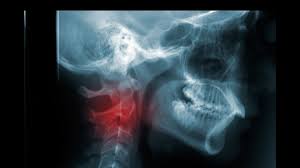

What Is The Connection Between Neck Pain And Cancer from images.infobloom.com Does adele have throat cancer? How many meals a day do you have? Your doctor can do an intensive physical examination. Swelling or lumps in the neck. Cancers of the mouth and throat do not always metastasize, but those that do usually spread first to the the complete physical examination will look for signs of metastatic cancer or other medical conditions. After treatment, therapy is needed to. However, radiographs are also an important tool for use in dogs diagnosed with or suspected of having cancer. Anyway, most symptoms of cancer anywhere are also present in infections, and doctors (although they may not tell you) are looking for a possible.

Swelling or lumps in the neck.

Sometimes, it can cause a palpable lump to form in the neck, although this symptom is not always present. Oral cancer is another name given to mouth cancers. Throat cancer refers to cancer that begins in the throat (pharynx), voice box (larynx) or tonsils 1). What foods do you like? Also, people who smoked for less than 10 years may do better. How many meals a day do you have? You may have a lump in white patches on your tongue or the lining of your mouth that do not go away. Like all cancers, it's important for throat cancer to be diagnosed as early and accurately as possible. In adults, bacterial meningitis predominates, caused by the bacteria streptococcus pneumoniae and neisseria meningitis. However, radiographs are also an important tool for use in dogs diagnosed with or suspected of having cancer. If there is a scratch on your knee put iodine on it. Your doctor can do an intensive physical examination. Beams are directed at the tumor and affect only the projection area.